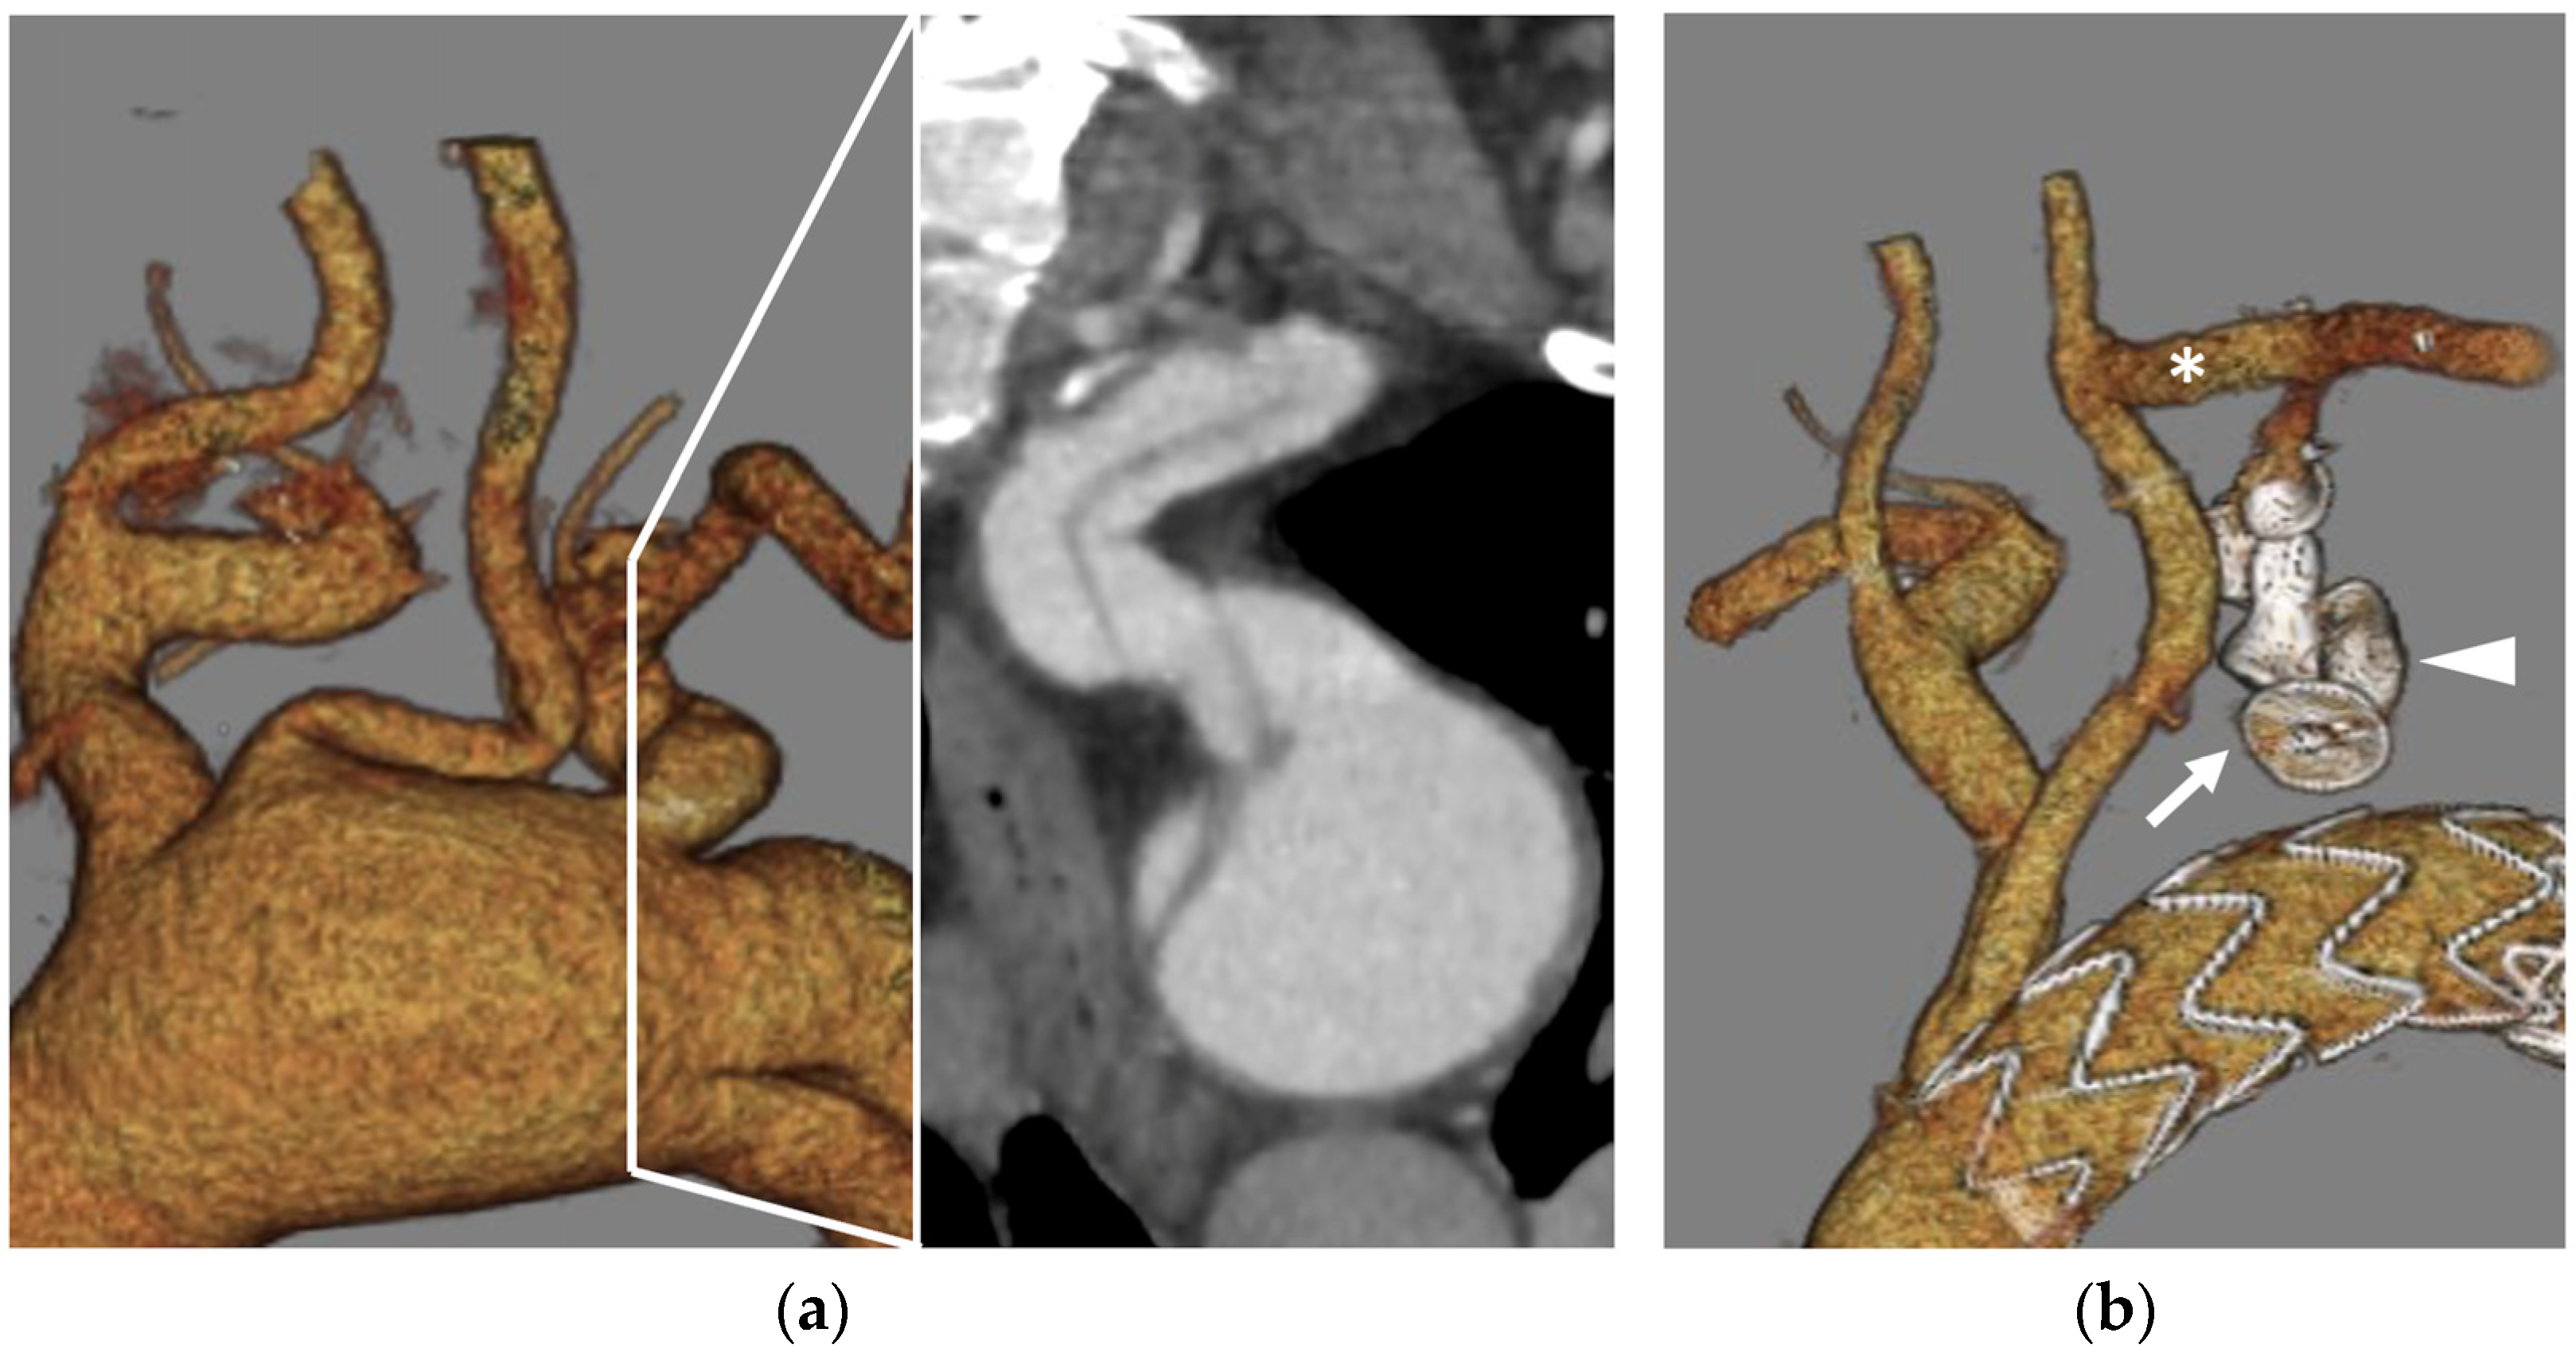

- As a modification of the original technique from Ferreira et al. [44], Tenorio et al. [45] suggested that branch elongation with a balloon-expandable stent before plug release should be the preferred choice in order to extend the sealing zone; the directional branch should be extended at least 20 mm beyond the branch cuff, and the plug should be released entirely within the stent, with no lobes protruding on the outside (Figure 6a). This configuration would limit any plug migration caused by short landing length inside the branch cuff.

- Alternatively, the “dog bone” technique [46] consists of deploying a balloon-expandable stent-graft inside the branch, sizing it 2 mm larger than the branch itself. It should be inflated to 8 mm, and the proximal and distal portions of the stent should be flared with a larger balloon (4 mm more than the branch diameter). An AVP II should then be released at the beginning of the narrowed part, thus creating a bottleneck effect.

- The MVP-7Q (MVP, Medtronic, Minneapolis, MN, USA) has also been used to occlude branches, with promising results in terms of early success and avoiding the use of a further bridging stent–graft, thus reducing overall procedural costs and possibly operating time [47] (Figure 6b). Aside from the economic and technical aspects, the MVP PTFE membrane design guarantees immediate vessel occlusion, which is of paramount importance in symptomatic/ruptured aneurysms, as opposed to the AVP II design which needs time to achieve complete branch thrombosis.